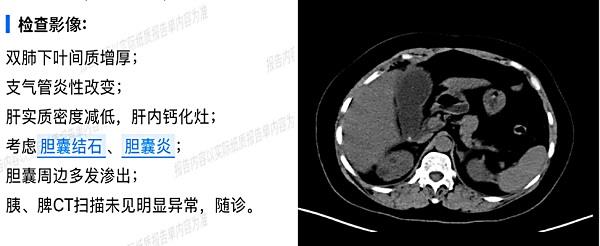

CT提示:胆囊结石伴胆囊周边渗出